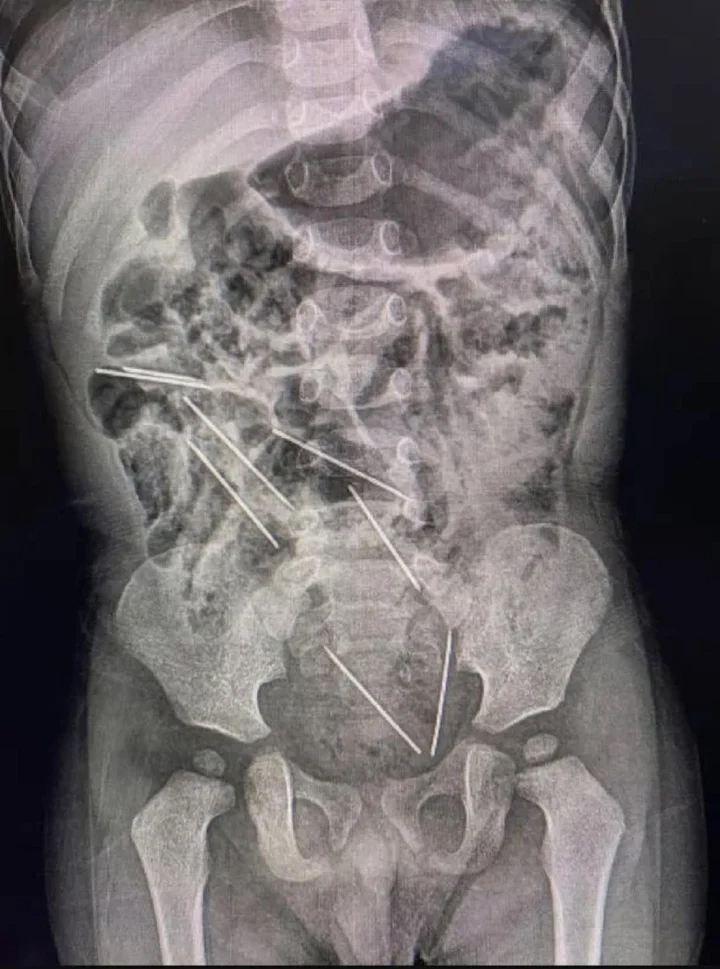

Kết quả chụp X-quang cho thấy, trong bụng cậu bé có 8 chiếc kim tiêm. Có 2 chiếc kim trong khoang bụng bên phải, 3 chiếc ở phía khoang bụng bên trái, 1 chiếc ở thành bụng và 2 chiếc khác nằm ở vị trí nguy hiểm giữa bàng quang và trực tràng.

Kết quả chụp X-quang cho thấy có 8 chiếc kim trong bụng cậu bé. (Ảnh: Jam Press)